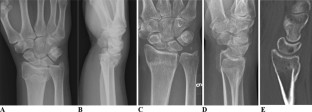

Fig. 1

Fig. 2

Fig. 3

Fig. 4

Fig. 5